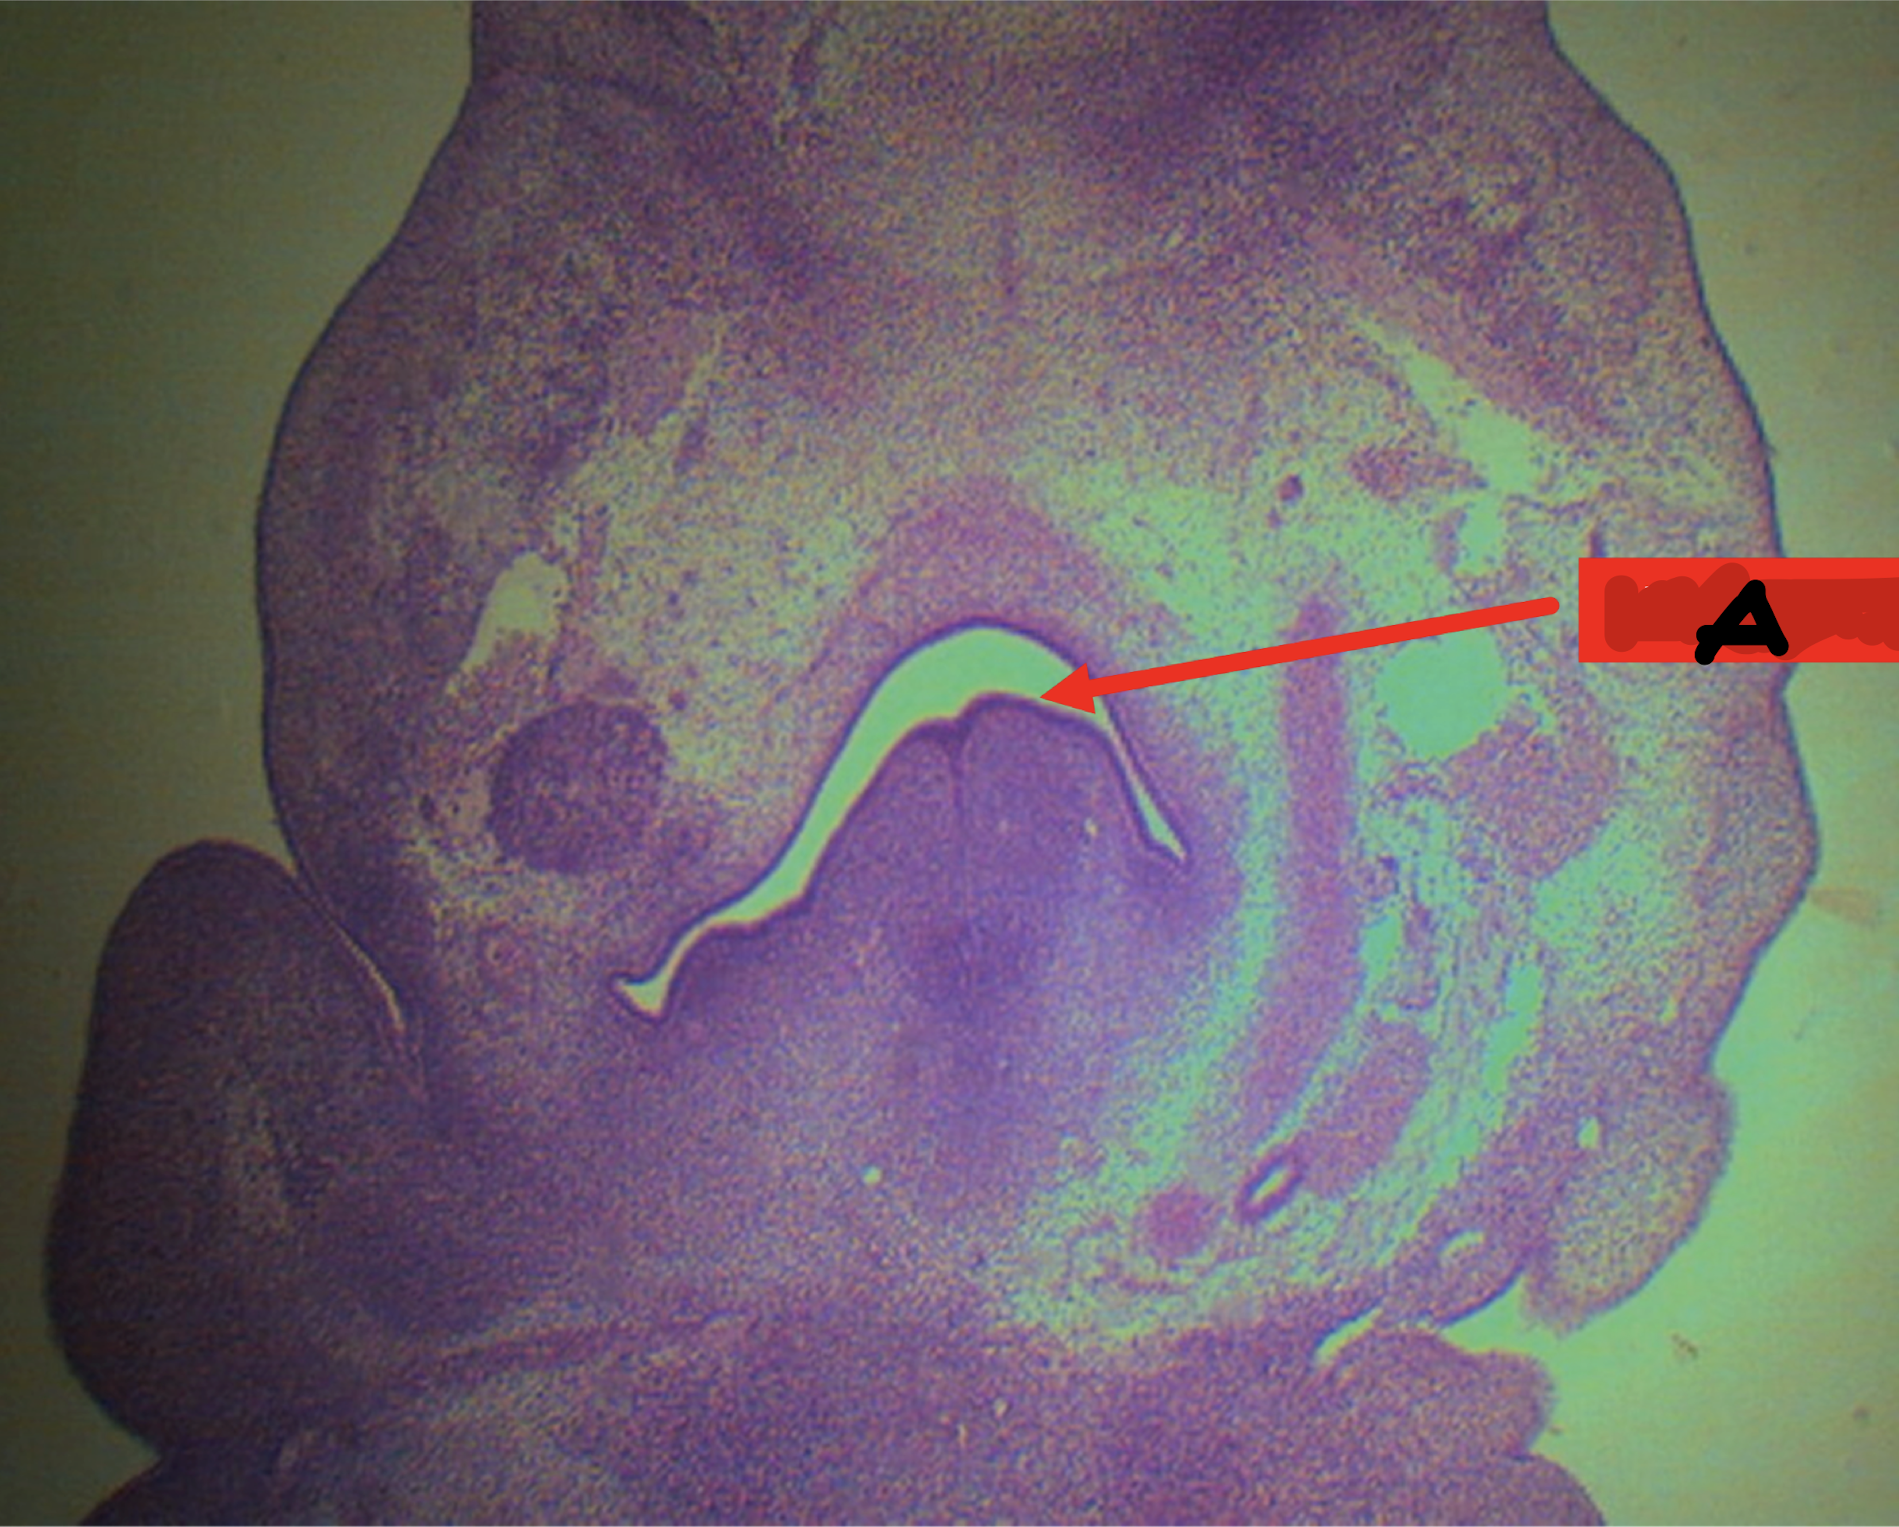

A: pharynx

Identify the structure